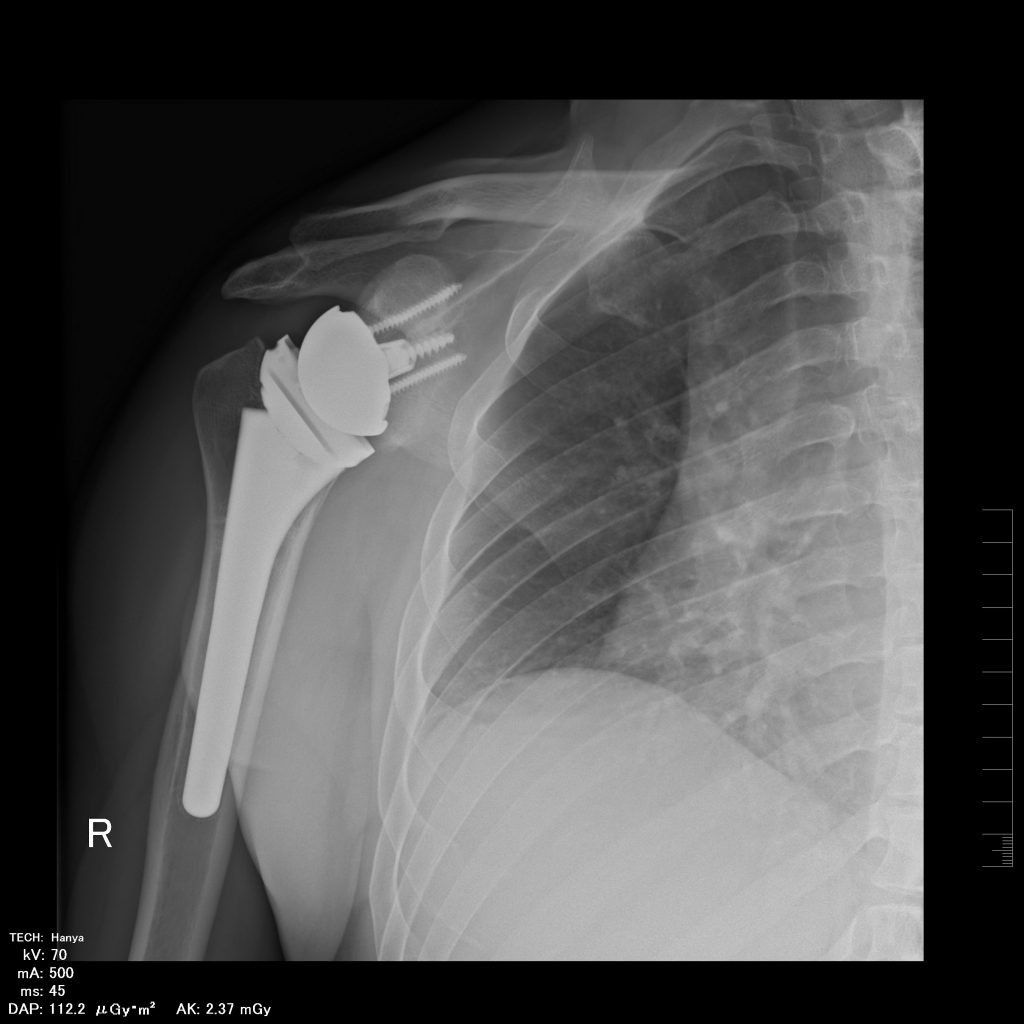

SHOULDER ARTHRODESIS

Operatively stiffening the shoulder is a very rare operation these days. It is done as a last resort to allow a stable foundation for the arm to function from. Though the motion between the upper arm and the shoulder blade is removed, the shoulder blade can still move quite a bit on the chest wall.

The following is a patient with an unstable replacement and an injury to his axillary nerve due to an unfortunate previous surgery. The condition is not amenable to another solution as the front part of the Deltoid muscle is no longer functional. An arthrodesis gives him a stable platform and a painless joint.